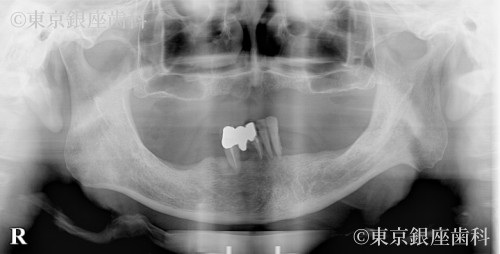

Before

疾患 歯牙部分欠損

知人の体験談から来院。左右サイナスリフトを伴う難しい手術だったが、痛みに敏感な中でも安心して完了。現在も調子よく経過。

上下ワンデイインプラント(サイナスリフト併用)